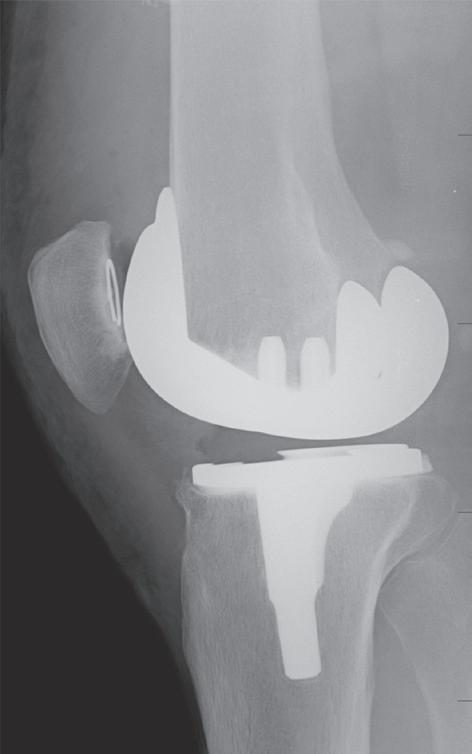

Při poškození pouze mediálního kompartmentu kloubu bez větší osové odchylky je metodou volby hemiartroplastika za použití speciálního implantátu (obr. 19.10, obr. 19.11). Tento výkon pacienta poměrně málo zatěžuje a rehabilitace je jednodušší než u osteotomie nebo totální endoprotézy. Podmínkou je nepoškozený přední zkřížený vaz a dobrý stav patelofemorálního kloubu. U mladších nemocných si obvykle po přibližně 15 až 20 letech vyžádá výměnu za totální endoprotézu.

Při pokročilé destrukci povrchů více částí kloubu je indikována implantace totální endoprotézy (obr. 19.12). U standardní náhrady kolenního kloubu se provádí resekce kloubních ploch femuru i tibie. Součástí výkonu je i odstranění předního zkříženého vazu (obr. 19.13) a obou menisků. Zásadní pro stabilitu náhrady je zachování zadního zkříženého vazu (pro předozadní stabilitu) a obou postranních vazů (pro stranovou stabilitu).

Obr. 19.11: Hemiartroplastika – předoperační (a, b) a pooperační rentgenový snímek (c, d)